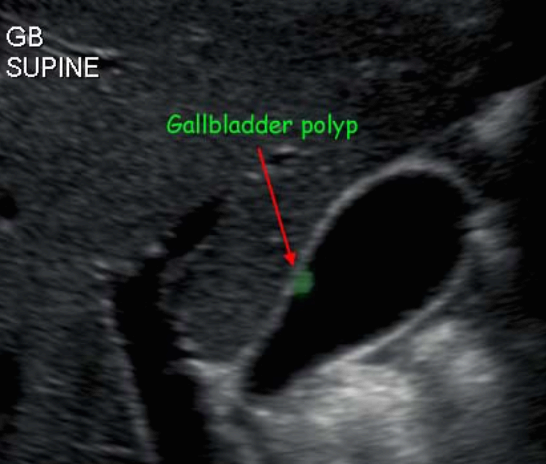

담낭 용종 ( GB polyp ) 담낭 안쪽 벽에서 담낭 안으로 돌출된 다양한 형태의 점막이 두꺼워진 것이다. 용종 자체로는 큰 문제를 일으키지 않으나, 용종의 크기가 커지면 암으로 변할 가능성이 높다. 용종의 크기가 직경 10mm 이상인경우 악성일 가능성이 높다.

발생빈도는 성인의 약 3~7% 정도이고 남성보다는 여성에서 2배 정도로 많으며 40대에서 많이 발생한다. 증상이 없으며 우연히 발견되나 드물게 명치끝이나 우상복부에 통증을 호소하는 경우도 있다.

1cm 이상의 담낭 용종은 수술로 담낭 전체를 제거하는 것을 원칙으로 하고, 1cm 미만인 경우는 주기적인 추적관찰을 한다. 용종의 크기가 1cm 미만이라 하더라도 담석이 동반되어 있거나, 증상( 복통, 담낭염등)이 있는 경우는 제거하는 것이 좋다.

- 1cm 미만의 고에코의 종괴 (hyperechoic mass) : 담석에 비해 에코가 낮고, 담낭벽보다는 고에코로 보임

- 담낭벽에 붙어 체위변화 시 이동이 없다

- 후방음영이 없다